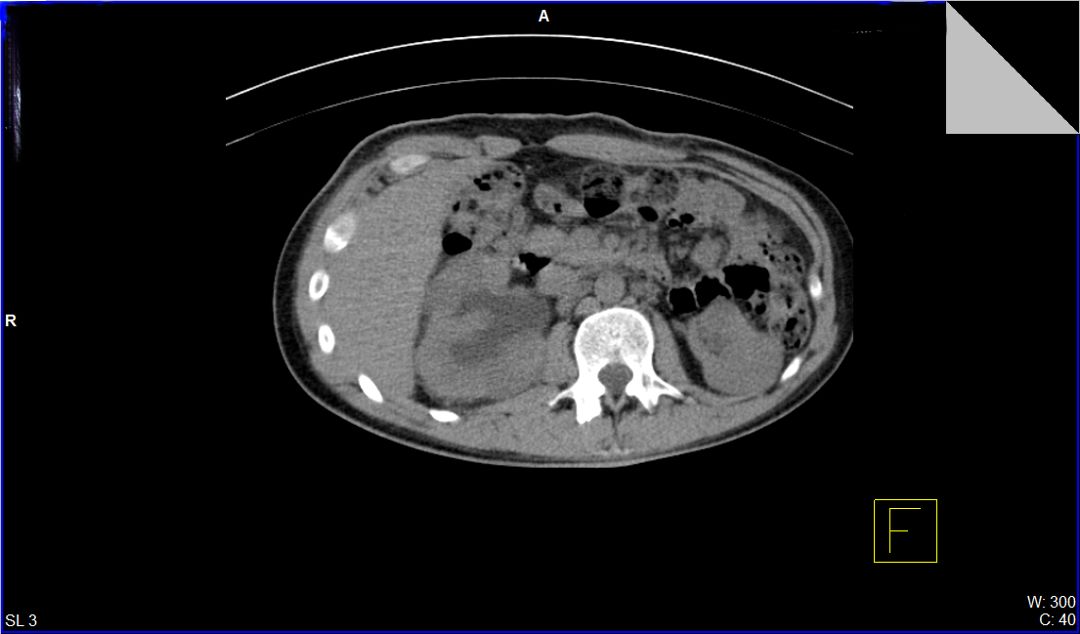

A 23-year-old male with a history of traumatic spinal cord injury (T3 ASIA A), iatrogenic urethral stenosis limiting clean intermittent catheterization (CIC), and low bladder capacity, was admitted for a planned open cystostomy and bladder stone extraction. Following stone removal, a 24-French SPC was placed. On postoperative day 3, the patient developed AD, characterized by hypertensive urgency and profuse sweating. Renal ultrasound revealed right-sided hydronephrosis. A CT scan confirmed SPC misplacement, with the catheter tip located inside the right distal ureter.

Figure 3 Axial view of the SPC's tip in the distal right ureter